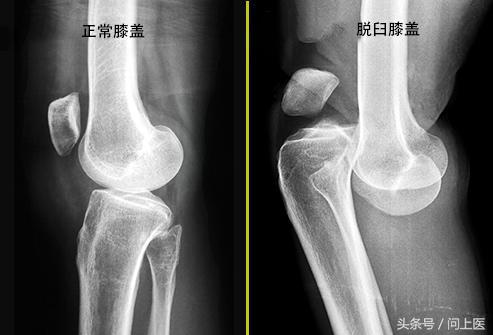

1. 脱位和骨折

如果撞击或摔倒严重损伤了膝盖,则可能会导致受损部位的骨骼(股骨、胫骨或膝盖骨)断裂或脱位,需要立即就诊。有时,骨折发生得较为缓慢,因为它会造成股骨末端出现微小裂缝,所以当患者开始使用膝盖时,才会发展为骨折。